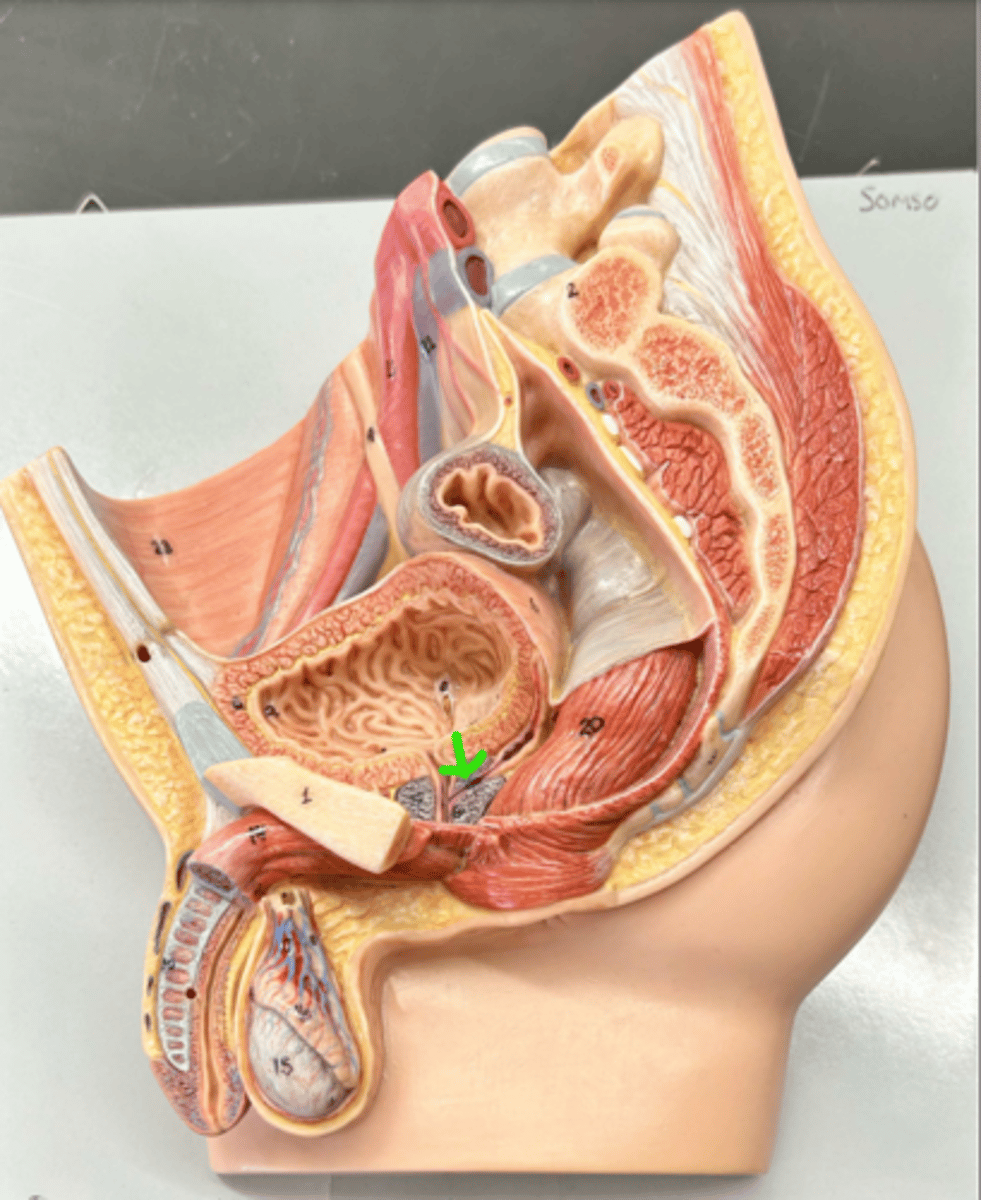

Prostate gland

Bulbourethral gland

Urethra

Urethra

Prostatic urethra

Membranous urethra

Spongy urethra